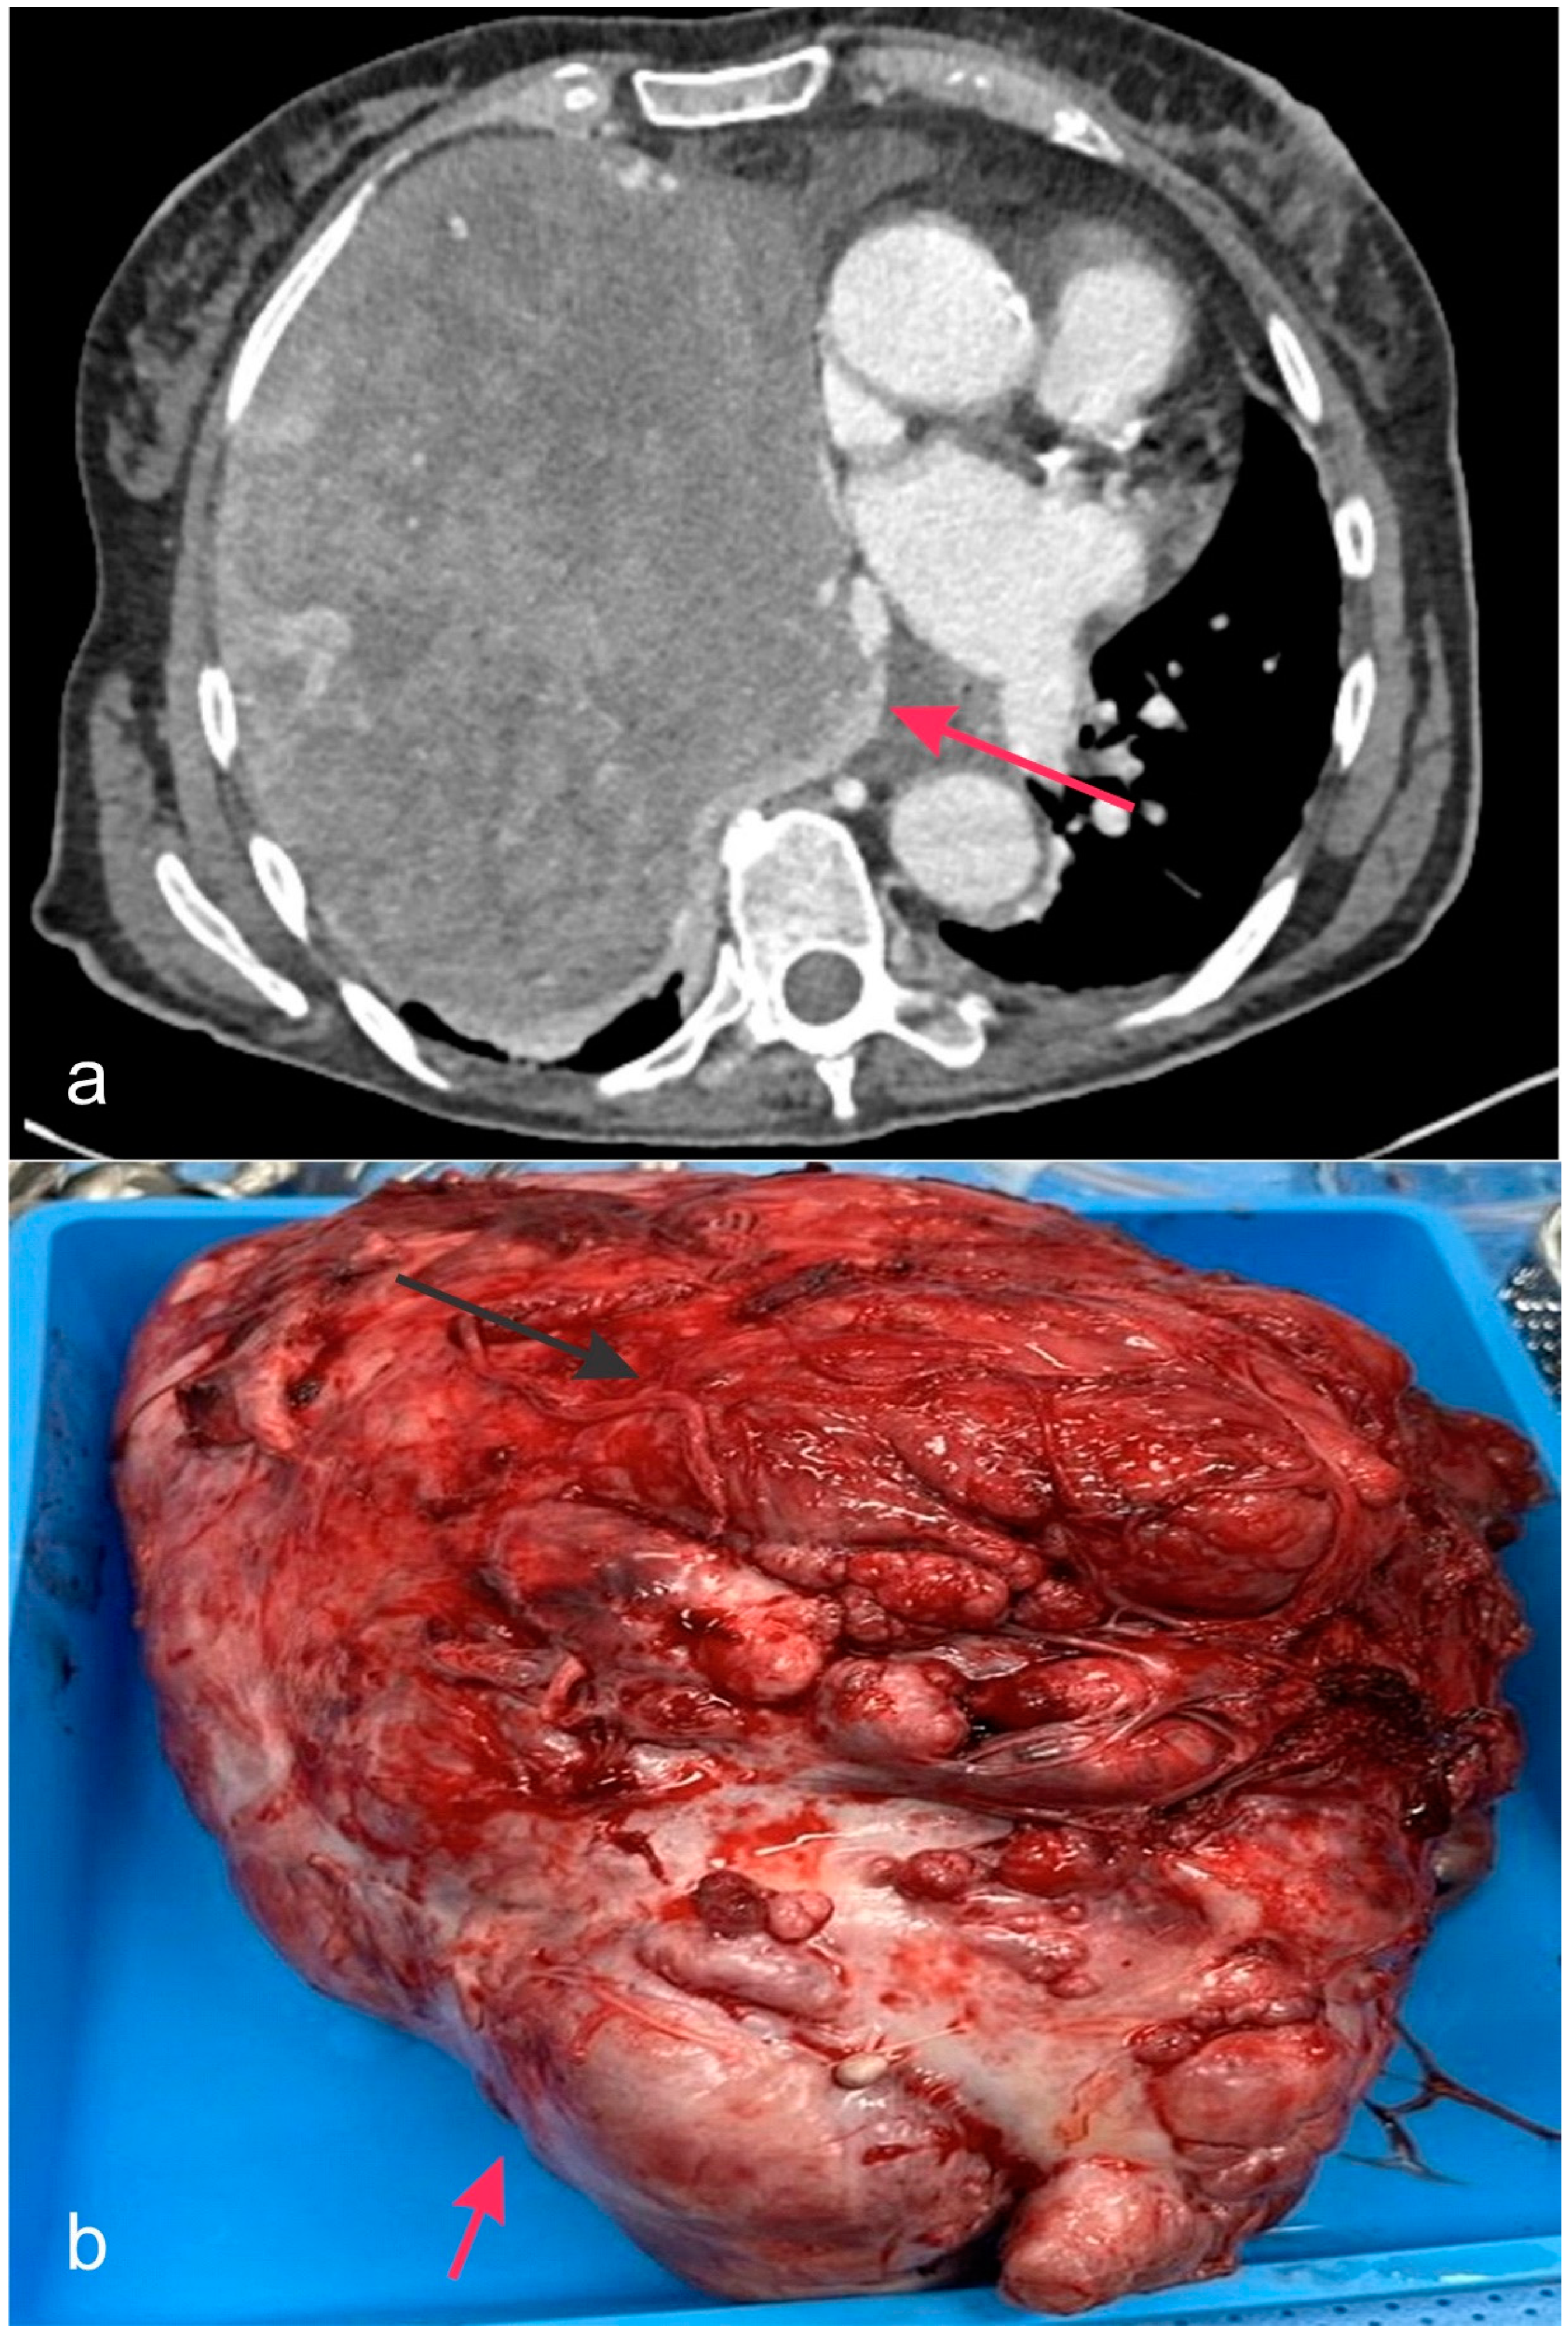

- Narin Tongal, S.; Yilmaz, O.; Ozguven, A.A.; Yuksel, H. DICER1 Syndrome: Coocurrence of Pleuropulmonary Blastoma and Cystic Nephroma. J. Bronchol. Interv. Pulmonol. 2024, 31, 94–97. [Google Scholar] [CrossRef] [PubMed]

- Berber Hamamci, M.; Yesil, S.; Bicakcioglu, P.; Gursoy, T.R.; Agackiran, Y.; Kurucu, B.; Kilci, A.C.; Gok, S.U.; Fettah, A.; Sahin, G. DICER1 syndrome with hepatoblastoma and pleuropulmonary blastoma. Pediatr. Blood Cancer 2024, 71, e31285. [Google Scholar] [CrossRef]